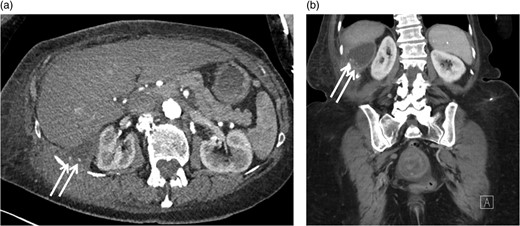

Clinical evaluation of her flank soft tissue tumor demonstrated a tender, non-erythematous, non-fluctuant 7 × 5 cm mass. Biochemical testing, including white blood cell count, was within normal limits. Computed tomography (Fig. 1a) demonstrated a 9.0 × 3.6 cm soft tissue mass and a 6.2 × 3.2 cm fluid collection abutting the right hepatic lobe and right kidney and extending into the abdominal wall. The CT findings were non specific, but the presence of a solid component with enhancing nodularity was suspicious for a neoplasm.

Positron emission tomography-computerized tomography revealed hypermetabolism (Fig. 1d) with maximum Standard Uptake Value of 13.4 g/ml. No overt metastatic spread was identified. The patient was referred for STS multi-disciplinary evaluation including discussion at Sarcoma Tumor Board. Careful review by a musculoskeletal radiologist highlighted the presence of cholecystectomy clips, fascial plane violation and round foci of calcium density (Fig. 3a and b). This raised suspicion for possible retained gallstones, especially since the violation of fascial planes was atypical for STS.

Axial (a) and coronal (b) CT images with IV contrast demonstrating round foci of calcium within the cystic component of the mass involving the right retroperitoneal space.